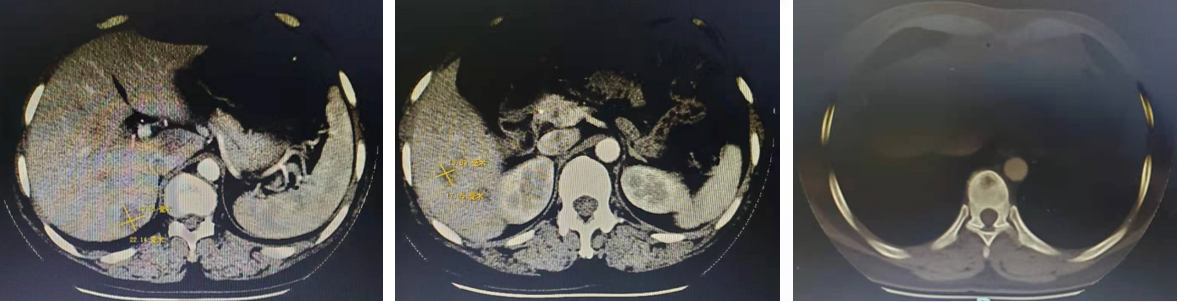

2017-03因腰部疼痛于我院就诊,2017-03-02行CT示:肝多发转移瘤,多发骨转移瘤。

Δ2017-03-02 CT检查

诊断:右乳癌术后肝转移、骨转移(HR-/HER2+)